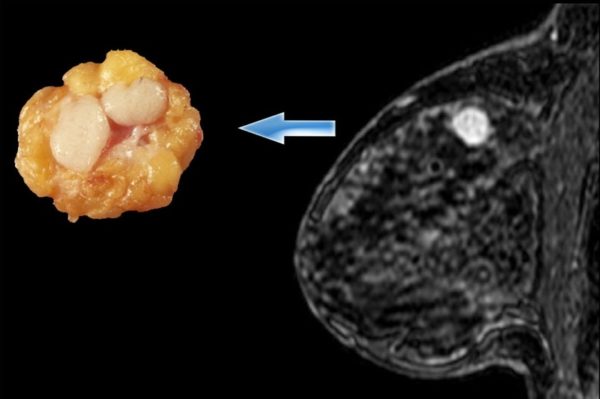

По-другому фиброзно-кистозную мастопатию называют фиброаденоматоз (представлен на фото).

Эта патология характеризуется быстрым разрастанием железистой ткани с образованием кист, заполненных жидкостью.